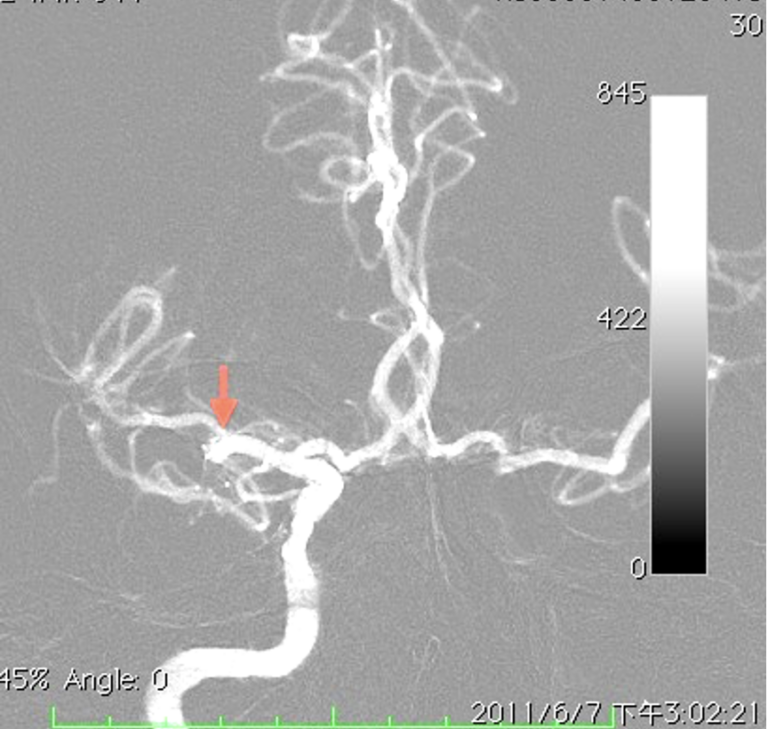

Overview of Common Neurovascular Disorders and Introduction of Minimally Invasive Endovascular Therapies 2026/3/12